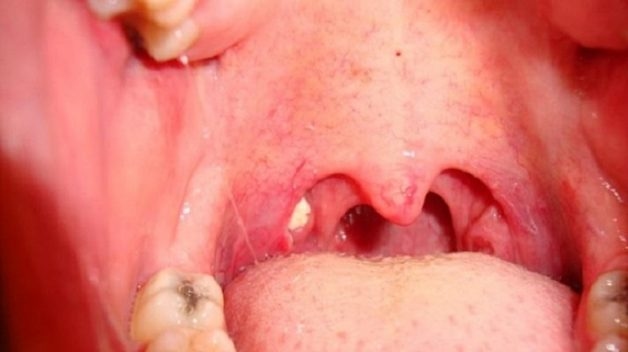

Nếu viêm họng là triệu chứng của bệnh viêm amidan, viêm xoang, trào ngược,… người bệnh cần chữa dứt điểm các bệnh này để chấm dứt dấu hiệu bệnh.

Nếu viêm họng là triệu chứng của bệnh viêm amidan, người bệnh cần chữa dứt điểm bệnh